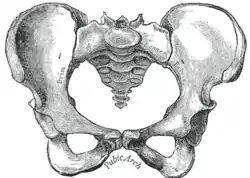

Joints of the pelvis. Anterior view. The arteries of the pelvis.